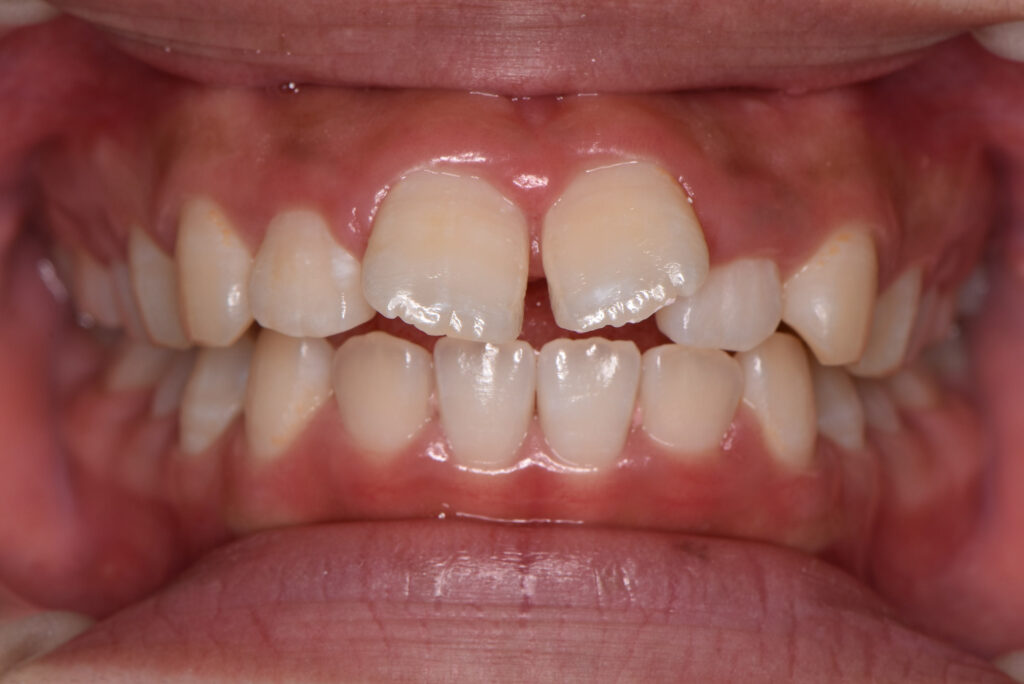

すきっ歯(正中離開)

すきっ歯とは、歯と歯の間に目立つすき間がある歯並びのことを指します。専門的には「空隙歯列(くうげきしれつ)」と呼ばれ、特に上の前歯の中央が開いている状態は「正中離開(せいちゅうりかい)」といいます。

【すきっ歯の代表的なタイプ】

前歯の中央だけが空いているタイプ

全体的に歯と歯の間が空いているタイプ

歯が小さく、バランス的にすき間が目立つタイプ

見た目は似ていても原因は異なり、治療法の選択にも大きく関わります。